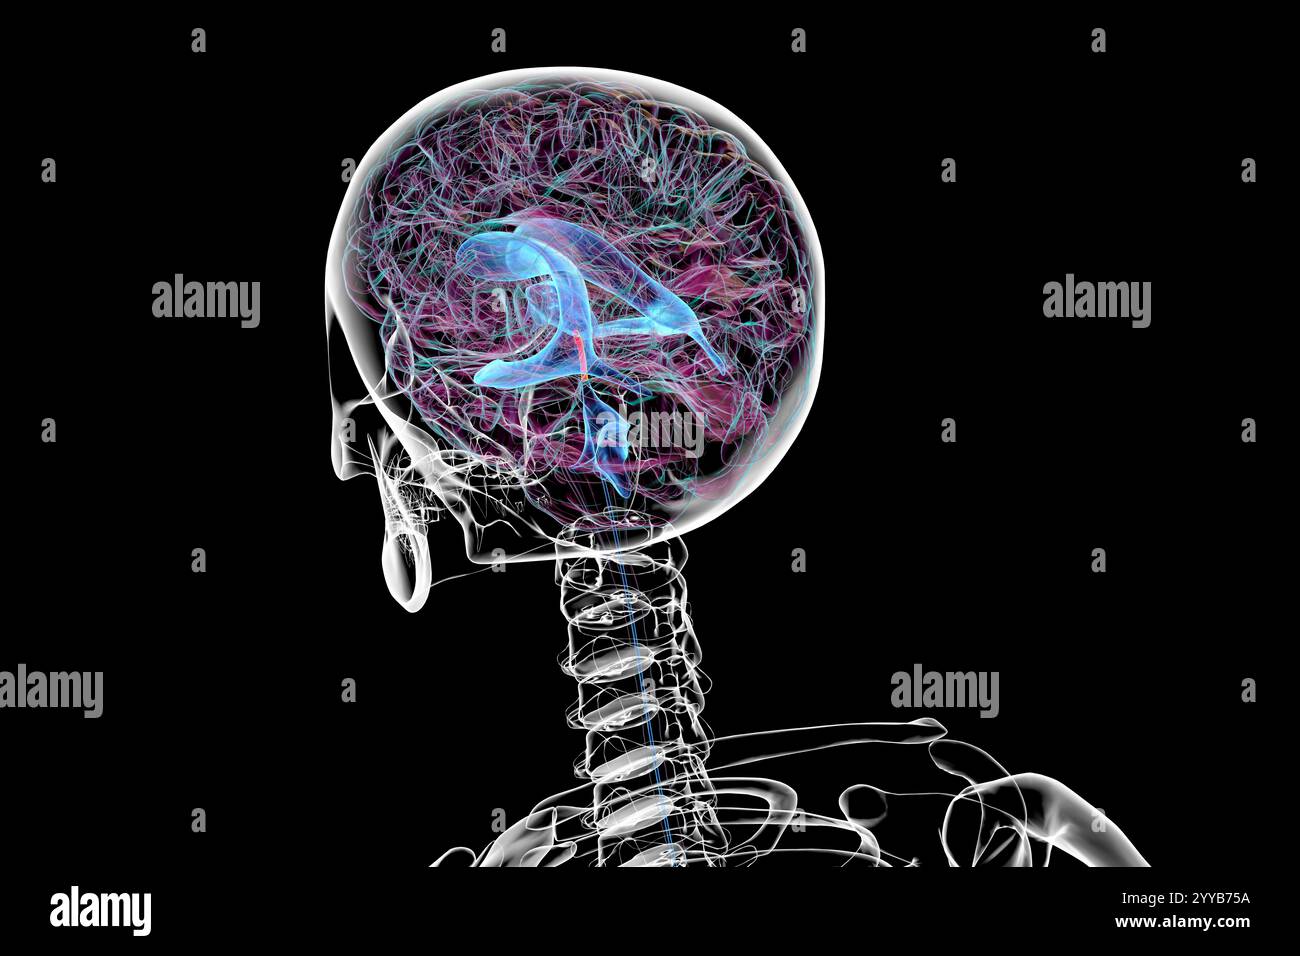

RF2T7NGWH–Ventrikel und zerebrales Aquädukt laterale Röntgenansicht 3D-Rendering-Illustration. Menschliches Gehirn und Ventrikelsystem Anatomie, Medizin, Gesundheitswesen, Scienc

RF2T7NGWK–Ventrikel und zerebraler Aquädukt lateral in Farben Röntgenbild-3D-Rendering-Illustration. Menschliches Gehirn und Ventrikelsystem Anatomie, medizinisch, gesund

RF2T7NGWR–Ventrikel und Hirn-Aquädukt-Röntgenprofil Nahansicht 3D-Rendering-Illustration mit Körperkonturen. Anatomie des menschlichen Gehirns und des Ventrikelsystems,

RF2T7NGWW–Ventrikel und zerebraler Aquädukt in Farben Röntgenprofil Nahansicht 3D-Rendering-Illustration. Anatomie des menschlichen Gehirns und des Ventrikelsystems, medizinisch,